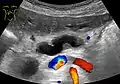

Ultrasonography of a dilated pancreatic duct (in this case 9mm) due to pancreatic cancer.

Compression, obstruction or inflammation of the pancreatic duct may lead to acute pancreatitis. The most common cause for obstruction is the presence of gallstones in the common bile duct, a condition called choledocholithiasis. Obstruction can also be due to duodenal inflammation in Crohn's disease.[7] A gallstone may get lodged in the constricted distal end of the ampulla of Vater, where it blocks the flow of both bile and pancreatic juice into the duodenum. Bile backing up into the pancreatic duct may initiate pancreatitis.[8] The pancreatic duct is generally regarded as abnormally enlarged if being over 3 mm in the head and 2 mm in the body or tail on CT scan.[9] Pancreatic duct or parts of pancreatic duct can be demonstrated on ultrasound in 75 to 85% of people.[10]